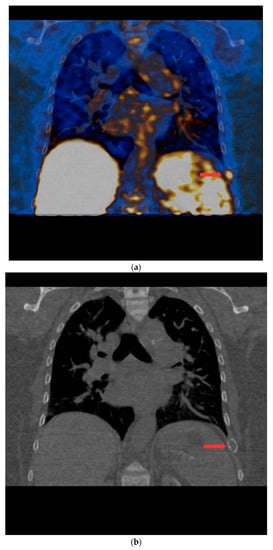

PET/CT with [11C]MET was performed on 19 patients, with negative results for both first-line imaging examinations. In this group, a positive result was obtained in 89.5% of the patients (17/19) (Figure 1 and Figure 2). In 2 patients (10.5%), the result was assessed as inconclusive (both of these patients showed accumulation of the radiotracer in a single lesion, the location and structure of which indicated that it might be a mediastinal lymph node; however, these lesions were not histologically verified due to revealed contraindications for surgery). Multiple lesions were observed in 57.9% of the patients (11/19) (Figure 3). Ectopic lesions were observed in 21.1% of the patients (4/19) (Figure 4). In total, 34 foci of increased accumulation of the radiotracer, considered as parathyroid glands, were observed. Additionally, in 15.8% of the patients (3/19), foci of increased accumulation of the radiotracer in the bones corresponding to brown tumors were observed (Figure 5a,b). Detailed results of the PET/CT examinations with [11C]MET are shown in Table 1.

Figure 1.

PET/CT with [11C]MET—frontal projection. Visible focus of increased radiotracer accumulation (red arrow) corresponding to the parathyroid gland below the right thyroid lobe.

Figure 5.

(a) PET/CT with [11C] MET—frontal projection. Visible focal increased radiotracer uptake (red arrow) corresponding to the brown tumor in the middle part of the left 9th rib. (b) Low-dose CT scan performed during PET/CT with [11C]MET in the same patient. In the location of the focus of increased accumulation of the radiotracer corresponding to the brown tumor of the left 9th rib, the distention of the contour of this rib is visible (red arrow).